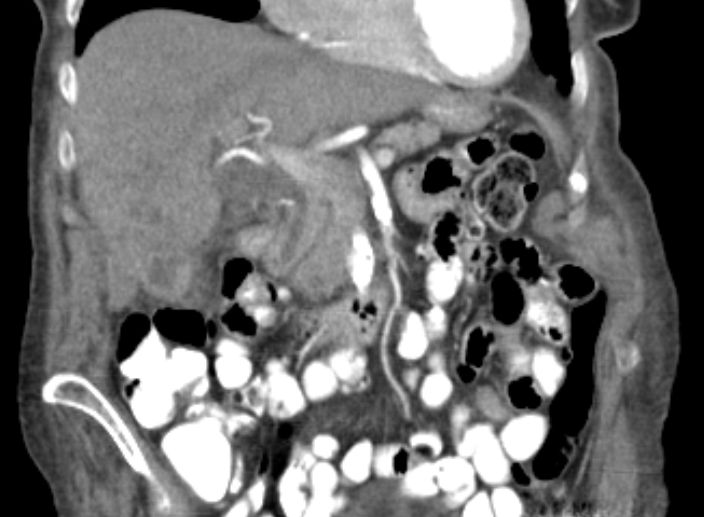

86-jähriger Mann, bei dem vor 9 Monaten eine Cholezystektomie wegen gedeckt perforierter Cholezystitis vorgenommen wurde. Jetzt Verdacht auf Leberabszess. Die laparoskopische Biopsie ergab ein Adenokarzinom. Die Nachbefundung der Gallenblase erbrachte immunhistochemisch den Nachweis eines Gallenblasenkarzinoms. | ||